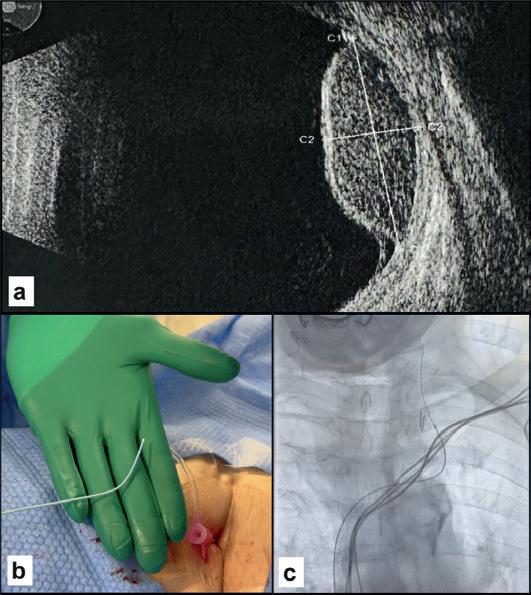

TWO

Female 60 years old

High-grade right frontal glioblastoma extending to the corpus callosum (A, B). Surgical histological confirmation but with negative tissue-based molecular testing. Pre-operative liquid biopsy from the right jugular vein (C) showing BRAF and PIK3CA mutations. Negative peripheral sample (D).

where venous sampling provides more effective molecular characterisation than peripheral sampling.

Liquid biopsy is beginning to be considered for use in diagnosis of lung nodules (Case one) for which no convenient solution is offered by imaging methods or percutaneous biopsy, which can prove inconclusive or unfeasible because of the associated risks.

Radiosurgery is increasingly used in cancer treatment, sometimes as the only option, with a consensus for its use in the absence of histological examination. Liquid biopsy can confirm the diagnosis and assess treatment response or resistance during follow-up. A liquid biopsy showing a mutation consistent with glial neoplasm (Case two) is decisive not only when histological diagnosis is not possible but also for monitoring treatment in the event of recurrence or progression. Molecular diagnosis has a higher success rate on cerebrospinal fluid than on peripheral blood but repeated lumbar puncture is not without risk for the patient. Retrograde percutaneous catheterisation of the jugular veins is an outpatient procedure known since its use in the diagnosis of pituitary tumours.

ASE THREE

Female, 83 years old

Uveal melanoma, left eye (A). Right transfemoral catheterisation of the left jugular vein (B, C) with finding of HNF1A mutation indicating a poor prognosis.